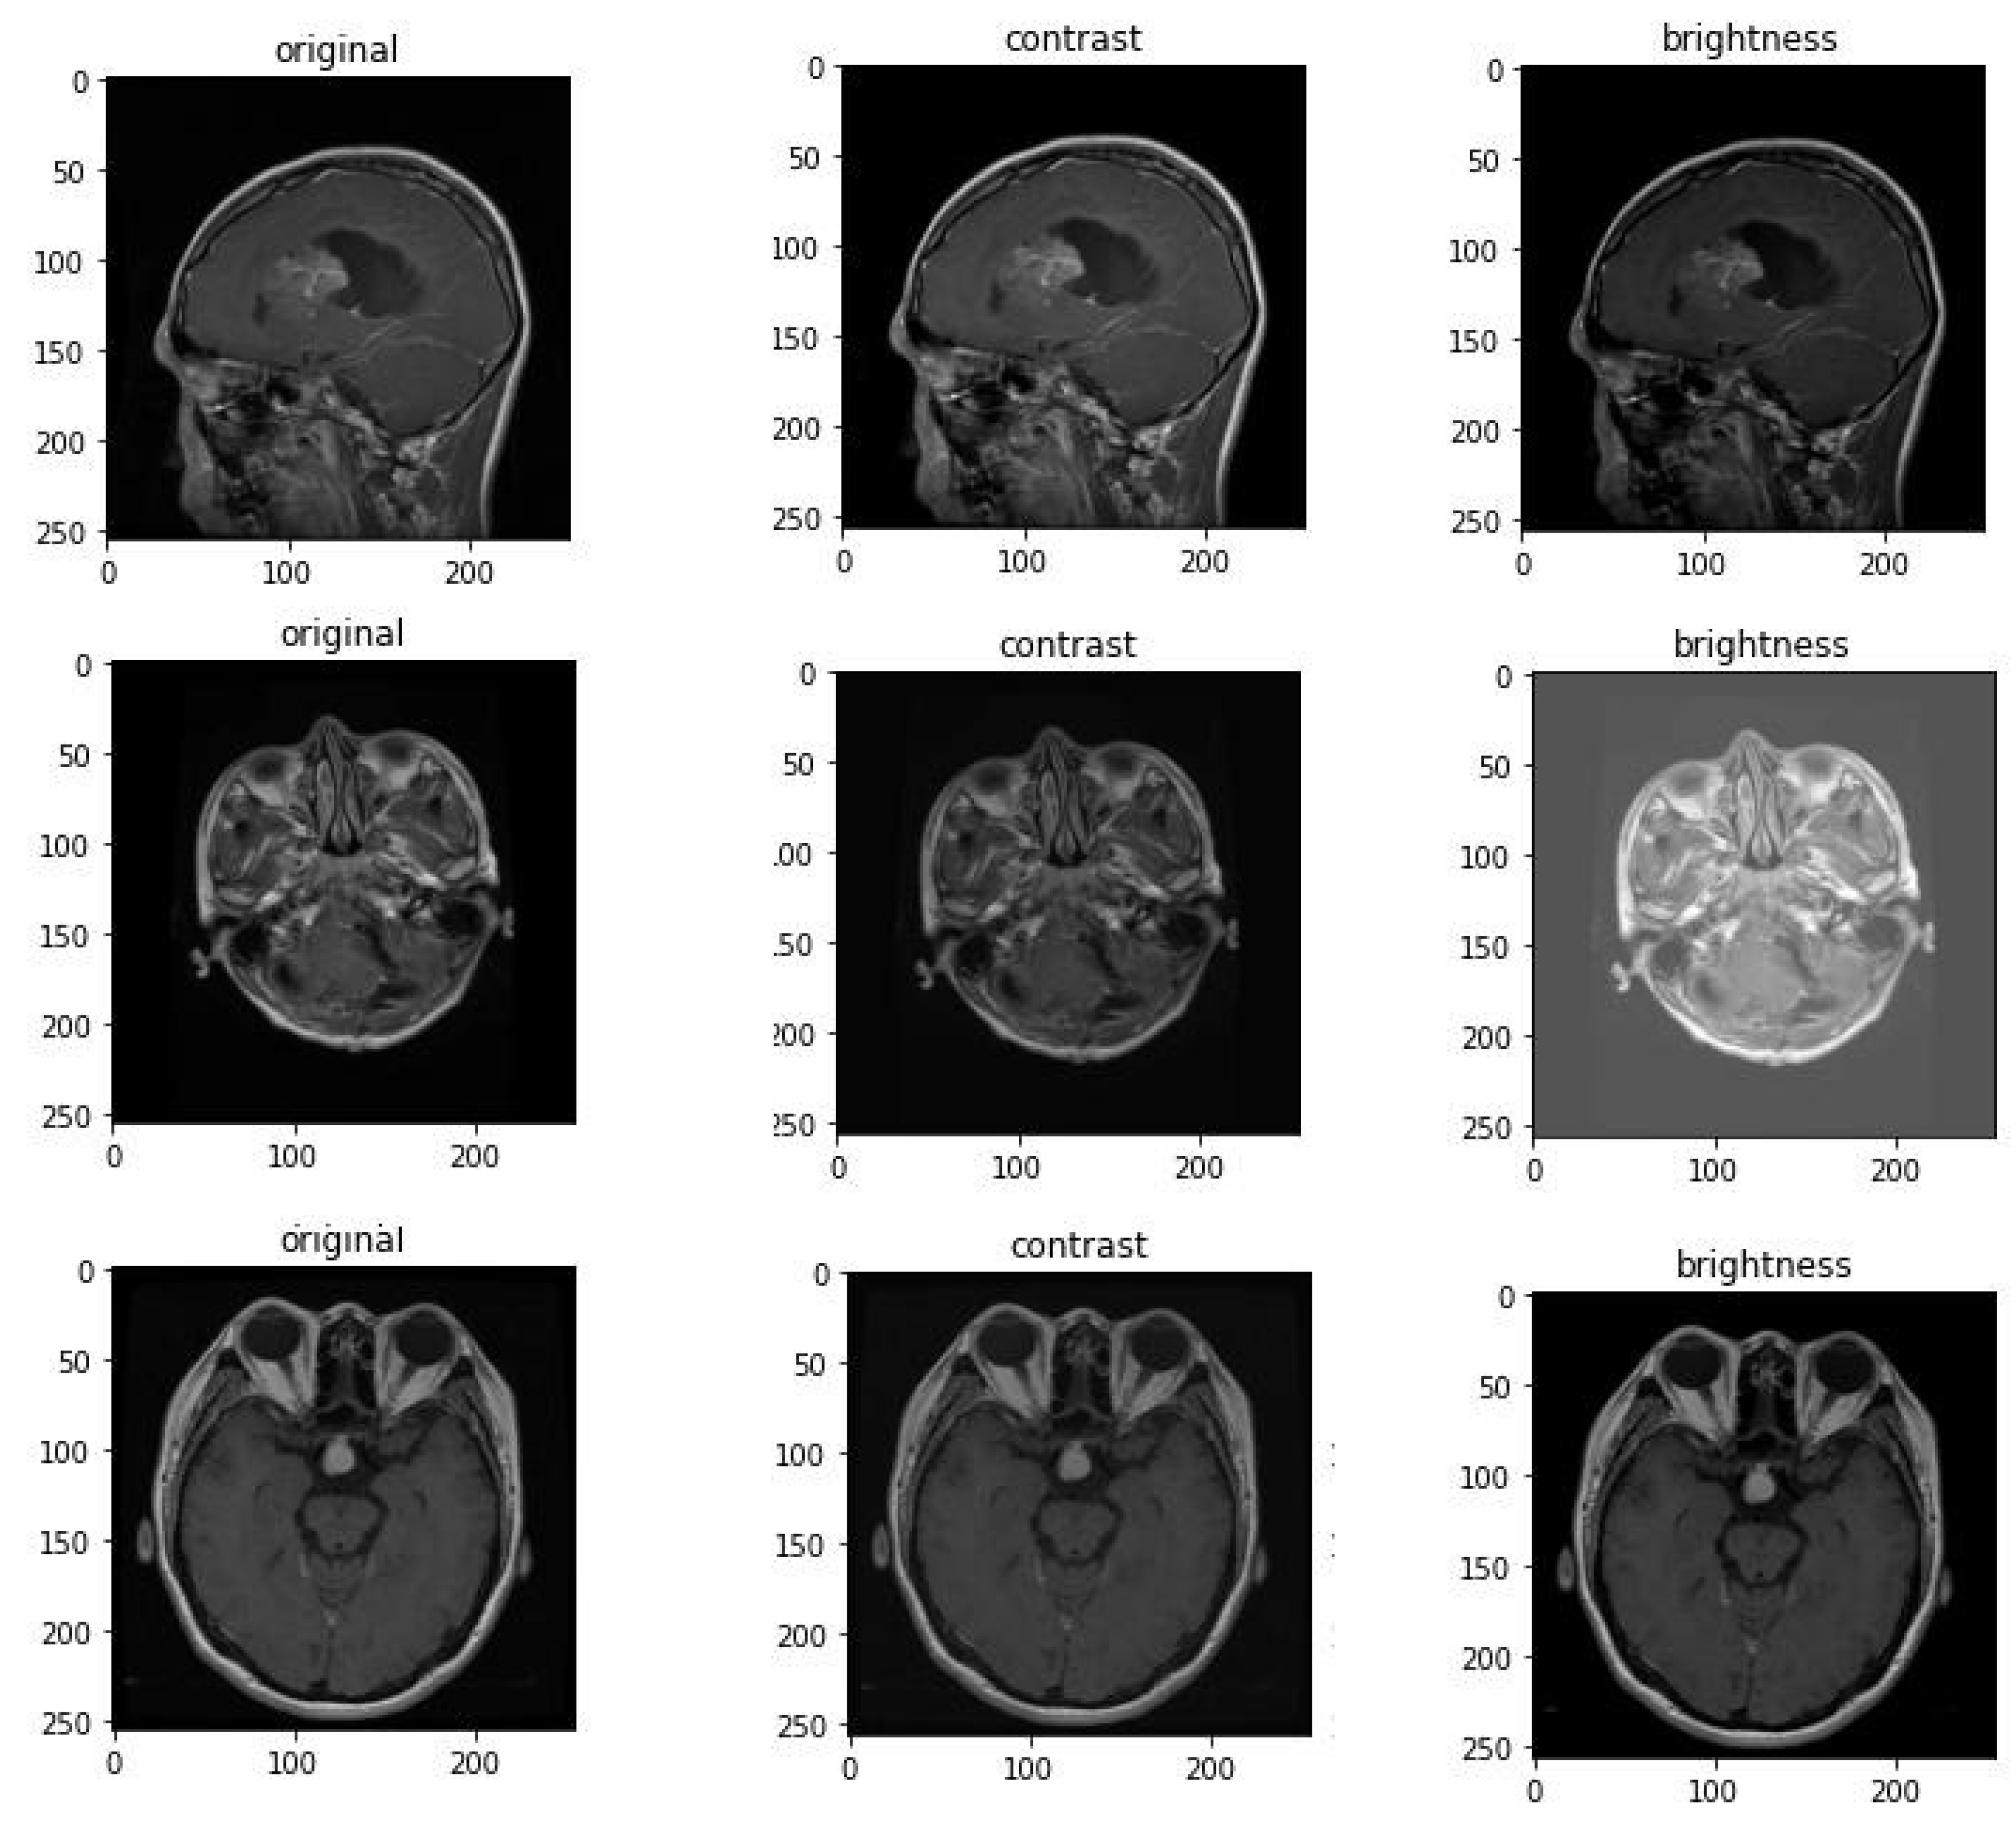

4.3. Images Pre-Processing

4.4. Data Augmentation